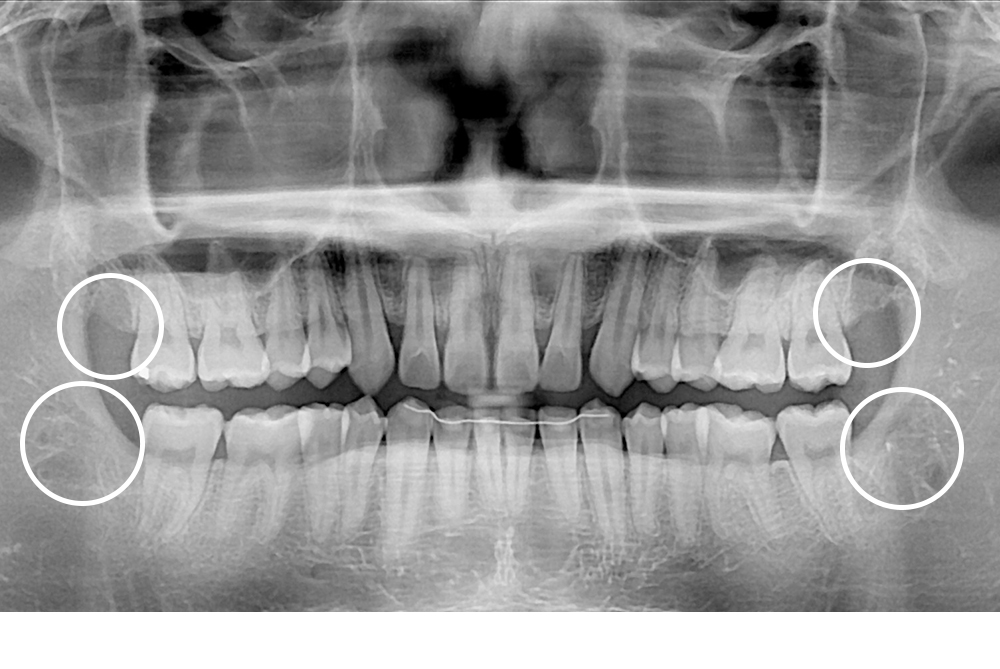

[사랑니] 매복 사랑니 발치

치료전 : 2017-08-22